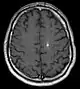

Diagnosis is generally made by magnetic resonance imaging (MRI), particularly using a specific imaging technique known as a gradient-echo sequence MRI, which can unmask small or punctate lesions that may otherwise remain undetected. These lesions are also more conspicuous on FLAIR imaging compared to standard T2 weighing. FLAIR imaging is different from gradient sequences. Rather, it is similar to T2 weighing but suppresses free-flowing fluid signal. Sometimes quiescent CCMs can be revealed as incidental findings during MRI exams ordered for other reasons. Many cavernous hemangiomas are detected "accidentally" during MRIs searching for other pathologies. These "incidentalomas" are generally asymptomatic. In the case of hemorrhage, however, a CT scan is more efficient at showing new blood than an MRI, and when brain hemorrhage is suspected, a CT scan may be ordered first, followed by an MRI to confirm the type of lesion that has bled.[14] Sometimes the lesion appearance imaged by MRI remains inconclusive. Consequently, neurosurgeons will order a cerebral angiogram or magnetic resonance angiogram (MRA). Since CCMs are low flow lesions (they are hooked into the venous side of the circulatory system), they will be angiographically occult (invisible). If a lesion is discernible via angiogram in the same location as in the MRI, then an arteriovenous malformation (AVM) becomes the primary concern.